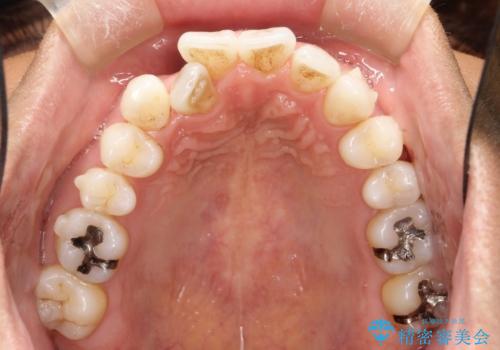

右上の前から2番目の歯が引っ込んで、下の前歯にはガタガタがありました。

上下の歯と歯の間を少量ずつ削りスペースを作り、インビザラインにて並べる計画としました。

目立たずに矯正治療を終えることができたことに満足していただけました。